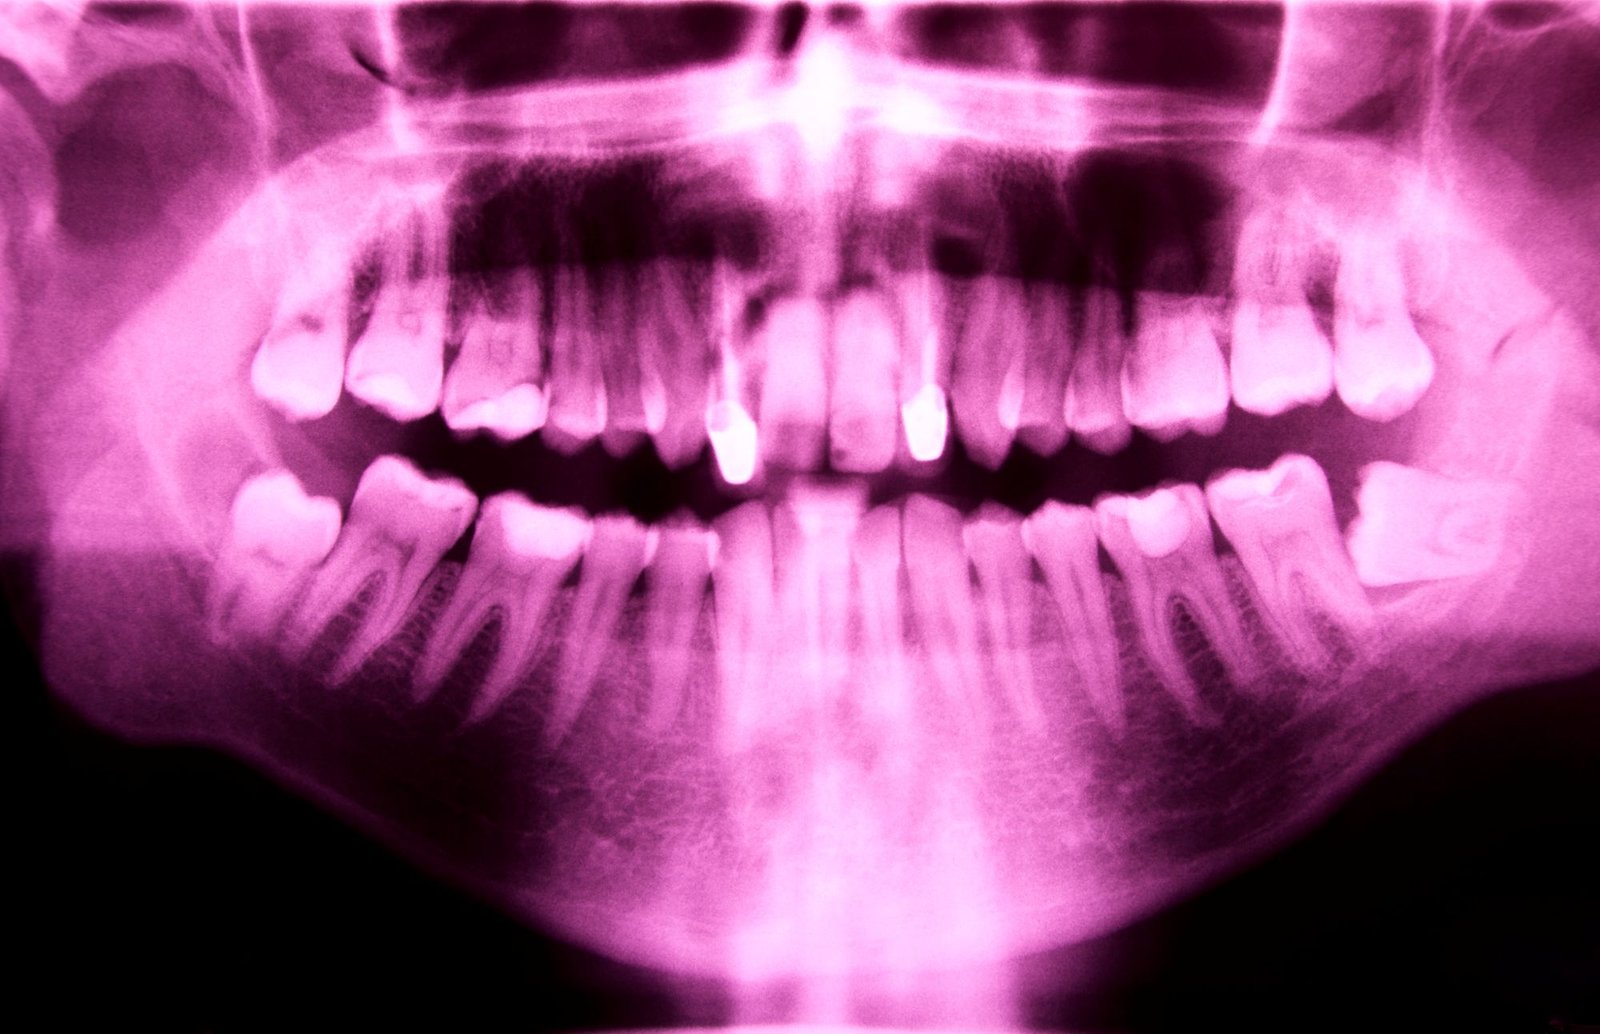

Estos alineadores están fabricados con materiales transparentes y biocompatibles que se ajustan perfectamente a la dentadura, moviendo los dientes de forma gradual y controlada. Gracias a la odontología digital, el paciente puede incluso ver una simulación del resultado final antes de empezar el tratamiento.

En Clínica RAdental, somos especialistas en tratamientos de alineadores que combinan estética, precisión y rapidez. Nuestro equipo planifica cada caso mediante escaneado intraoral y software 3D, garantizando resultados naturales y seguros.